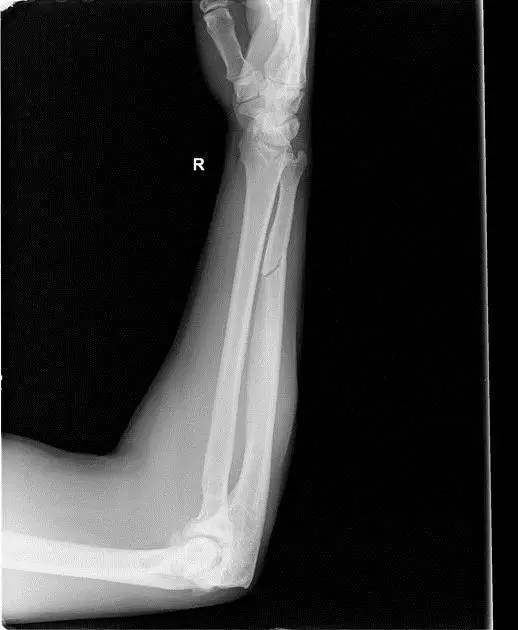

(3)Holstein lewis 骨折

肱骨远端 1/3 骨折伴桡神经嵌压。